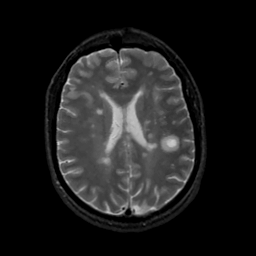

MR Study #16, June 23, 1991 -- Slice #31